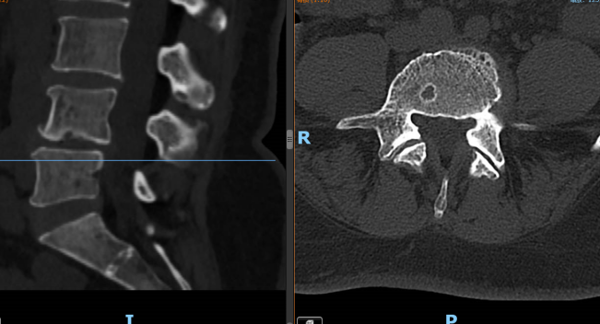

▲③术前CT片

“医生,我这半年来腰痛的厉害,右腿现在又痛又麻,走路都困难,有什么办法处理吗?”在骨科诊室,患者谭阿姨(化名)苦恼地说道。皇冠足球网 骨科脊柱外科专业专家欧裕福副主任医师详细询问谭阿姨病史,并为她安排了细致的检查,最终诊断为腰椎管狭窄症+腰椎滑脱症。

结合谭阿姨下腰部明显压痛、右下肢疼痛及活动障碍等症状,骨科脊柱外科团队经过多次术前讨论,并联合麻醉手术中心团队,为谭阿姨制定了个性化的诊疗方案,决定运用经皮内镜下腰椎减压融合技术为患者进行治疗。

术后第一天,医生为谭阿姨伤口换药并为他进行了腰椎X线及CT复查,显示手术后内固定植入物固定良好,椎间融合器放置在位,下肢麻木及疼痛症状明显好转。经过一系列的康复锻炼,谭阿姨术后第二天下床行走,术后5天办理出院。